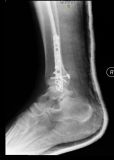

4. Fracture-dislocation of the right ankle in a 50-year-old male.

Treatment: 1st step, external fixation. 2nd step after 14 days, removal the external fixator and at the same time open reduction internal fixation (ORIF)

I. Before surgery, lateral x-ray shows the fracture of tibia and of lateral malleolus II. Post-surgery 1st step, the external fixator III. 2nd step, removal the external fixator and at the same time ORIF